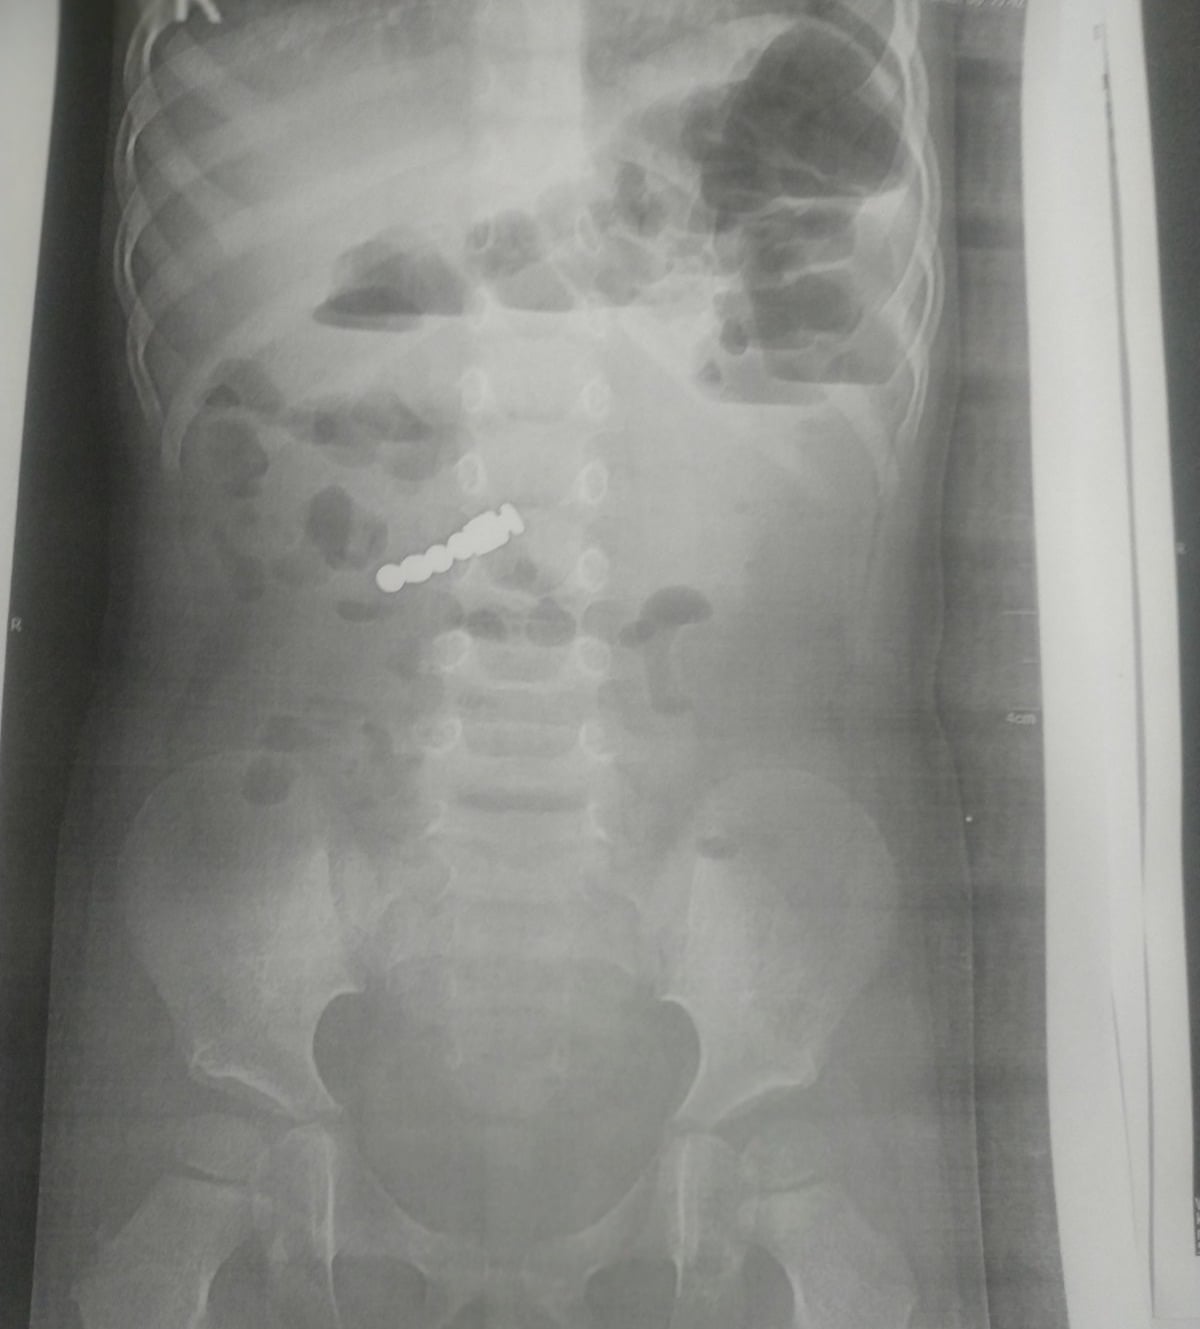

Серед симптомів у маленької пацієнтки були тільки блювання і підвищена температура. У районній лікарні їй зробили рентген, на якому видно 4 магнітики. Тоді дитину на «швидкій» госпіталізували до львівської лікарні.

Лікарі діставали магнітики з допомогою сучасного електронно-оптичного перетворювача (ЕОП) в ургентній операційній, що дозволило провести маніпуляції різного рівня складності. На третій день після отриманого медикаментозного лікування дівчинку виписали додому.